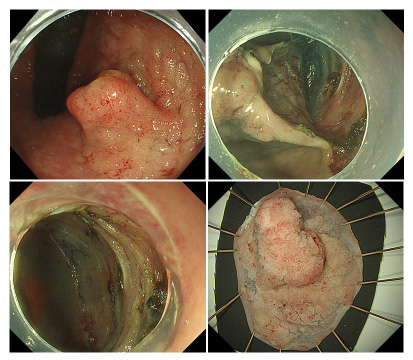

内視鏡治療

内視鏡を使って、大腸の内側から病変を切除する方法です。リンパ節転移がほとんどなく、技術的に可能な大きさ、部位にあるものが対象になります。内視鏡治療には内視鏡的ポリープ切除術(ポリペクトミー)と内視鏡的粘膜切除術(EMR)と内視鏡的粘膜下層剥離術(ESD)があり、病変の部位、大きさ、形、広がりによって治療法を選択します。手術と比べると、体に対する負担が少なく、がんの切除後も胃が残るため、食生活への影響が少ないという利点があります。

茎がなく、隆起がなだらかな病変に対して行われます。病巣粘膜の下に生理食塩水を注入して病変の粘膜を浮き上がらせ、スネアにて粘膜を焼き切る方法です。 - 内視鏡的粘膜下層剥離術(ESD)

EMRが困難な病変に対して行われる治療法です。病変を浮き上がらせるために、粘膜下層に生理食塩水やヒアルロン酸ナトリウムなどを注入してから、病変の周りを高周波ナイフで徐々に切開して剥ぎ取る方法です。EMRに比べると治療時間も長くなり、出血や穿孔のリスクも少し高くなります。

早期大腸癌に対する粘膜下層剥離術(ESD)